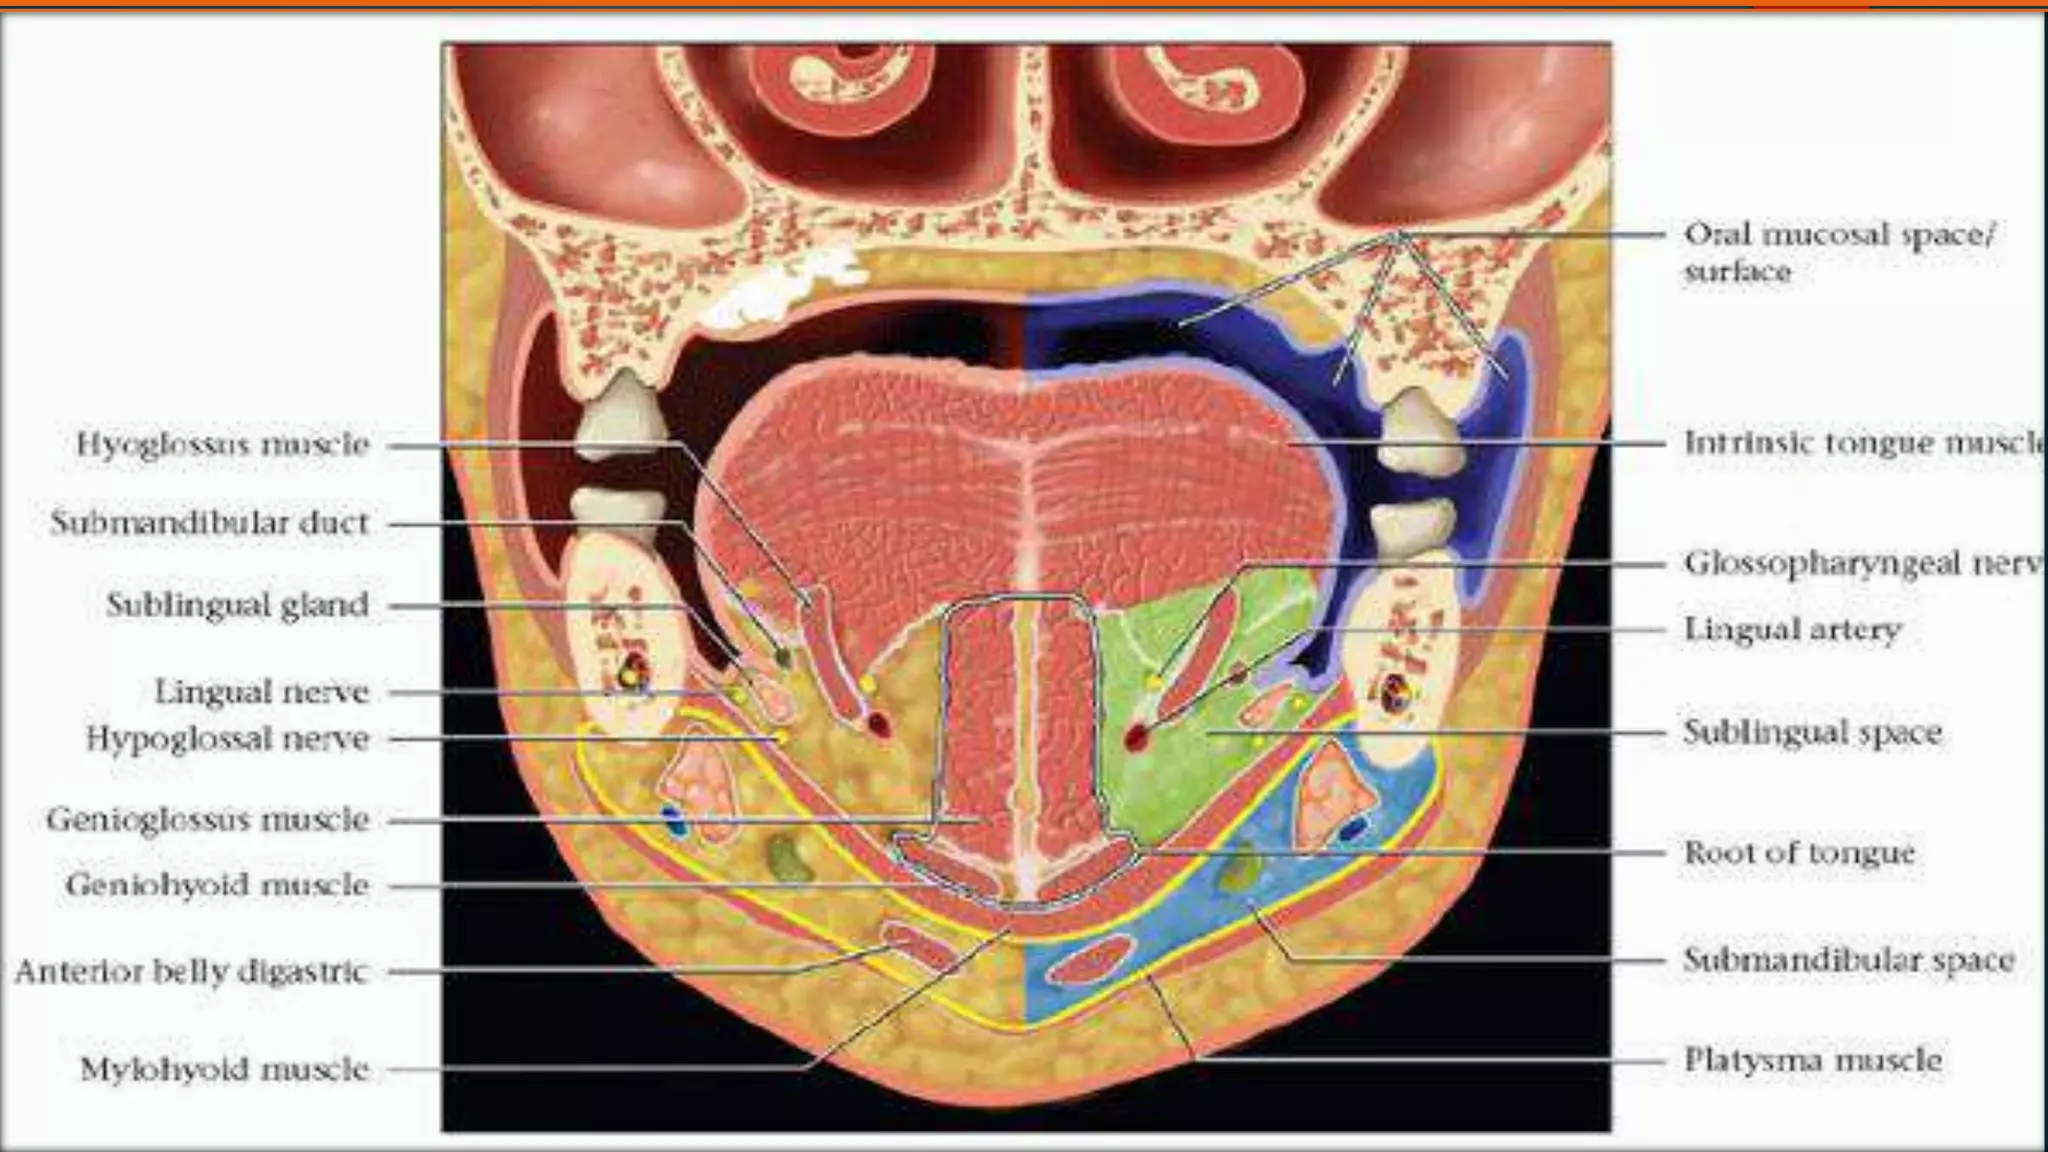

SUBLINGUAL SPACE

Extent : Above the mylohyoid muscle

Contents : Sublingual gland and their ducts , LNs, hypoglossal muscle , lingual

artery and vein , hypoglossal N and deeper portion of submandibular gland.

SUBMANDIBULAR SPACE

 Extend : Mylohoid superiorly & hyoid

bone inferiorly.

 Communicates freely with sublingual

space.

 Contents : superficial portions of the

Submandibular gland, submental and

submandibular LNs, facial artery and

vein, fat and ant belly of digastric.